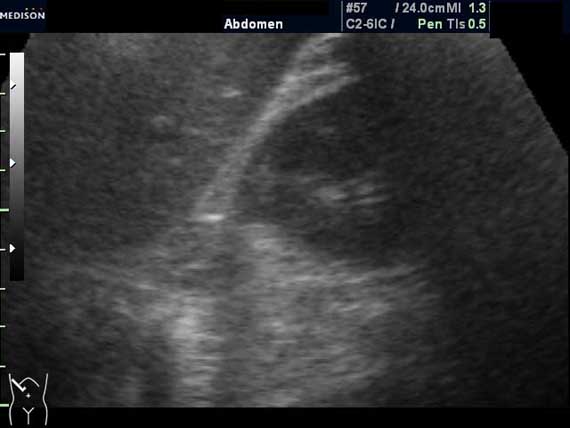

Женщина 50 лет. Жалоб нет. Обследование перед поездкой в санаторий по поводу дисфункции гепатобилиарной системы.

Случайная находка в нижней трети левой почки (не в полюсе, а по задне-медиальной поверхности).

Образование в левой почке

Согласен. Именно с таким диагнозом (ангиомиолипома) отправил на КТ. Особенностью случая ИМХО является заметный "выход" образования за контур почки (на 2/3 объема).

При ультрасонографии ангиомиолипома выглядит как округлое образование без капсулы с однородной внутренней эхоструктурой и четкими контурами; эхогенность ее чаще всего равна или чуть выше эхогенности перинефральной клетчатки [7]. Значительно реже эхогенность ангиомиолипом может быть равна эхогенности почечной паренхимы; такие опухоли состоят почти полностью из гладкомышечной ткани [8]. Иногда позади ангиомиолипомы может определяться слабая акустическая тень.